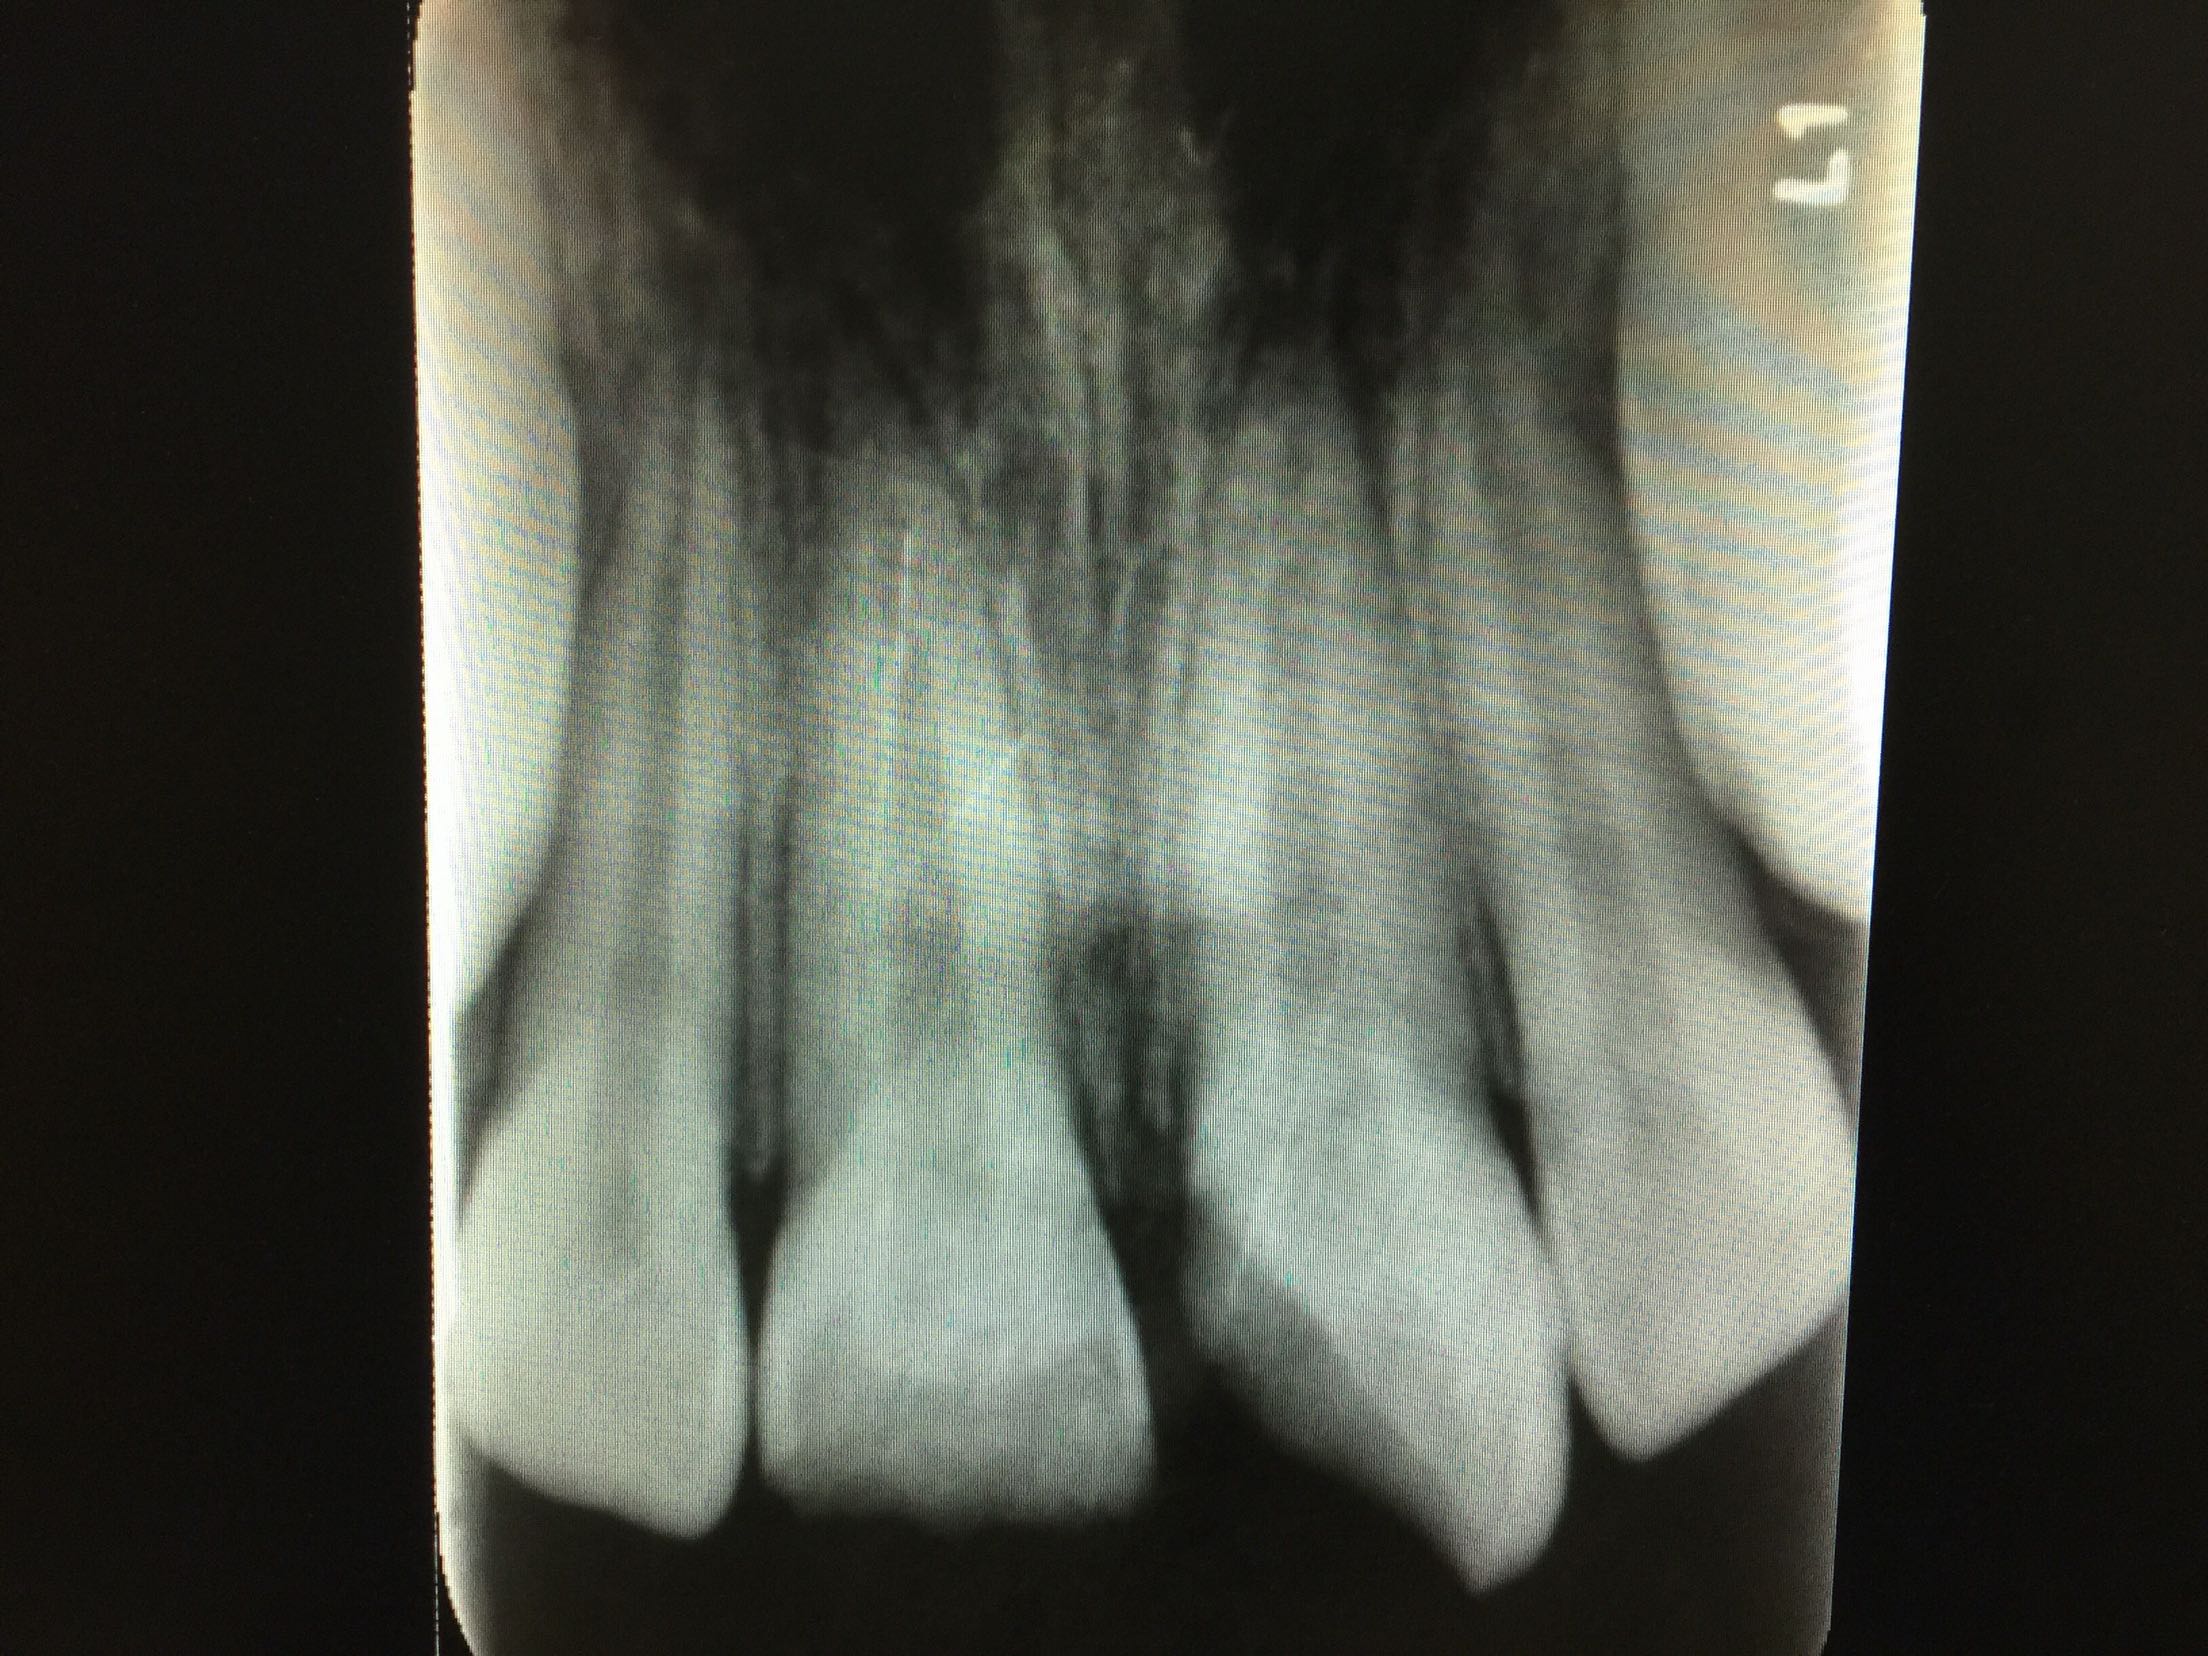

复诊,11,21牙进口玻璃离子垫底,前牙美容修复术调合,抛光。 3周后复诊:牙髓电活力测试11牙14,21牙15。 拍片:

11,21牙牙周膜腔未见明显增宽,很尖周无暗影。 建议继续拍片观察。 一月后复诊:牙髓电活力测试11牙13,21牙15。 拍片:11,21牙牙周膜腔未见明显增宽,很尖周无暗影。 建议11,21前牙树脂功能修复。 处置:行11牙,21牙牙树脂修复术。继续观察,约复诊。